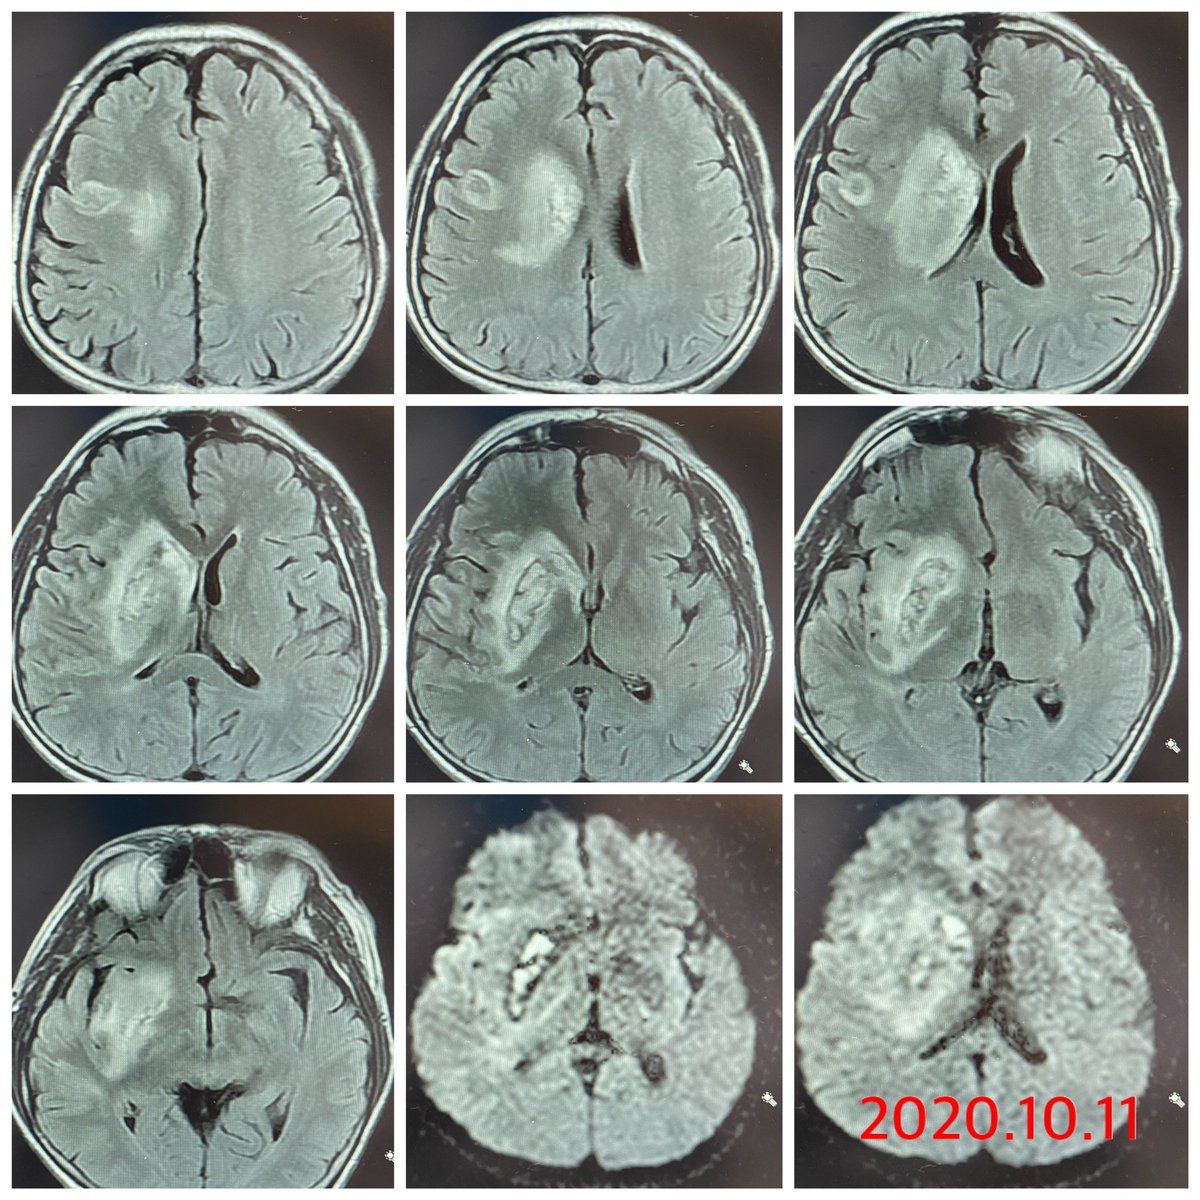

To be continued Immediate postprocedure & FU imaging changes Hemorrhagic transformation Fortunately no stent implantation & clinical situation improving. Question: 1. how to use anti thrombotic? 2. How to manage the residual carotid stenosis?